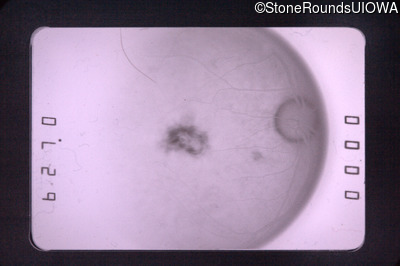

Fluorescein Angiography - Left - 20/400

Exemplar